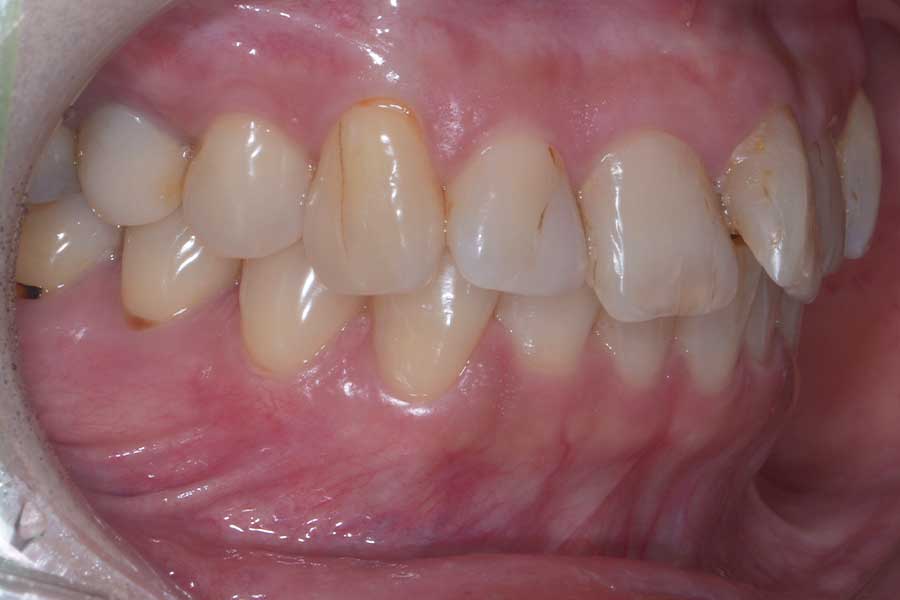

治療前

主訴 前歯の虫歯治療の前に飛び出た前歯を引っ込めたい

治療内容 上顎ラビアル矯正(表側矯正)